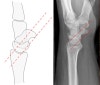

Cf) Capitolunate instability

* Capitolunate angle

The capitate axis joins the midportion of the proximal convexity of the third metacarpal and that of the proximal surface of the capitate.

Capitolunate angle > 30º indicates instability of the wrist.